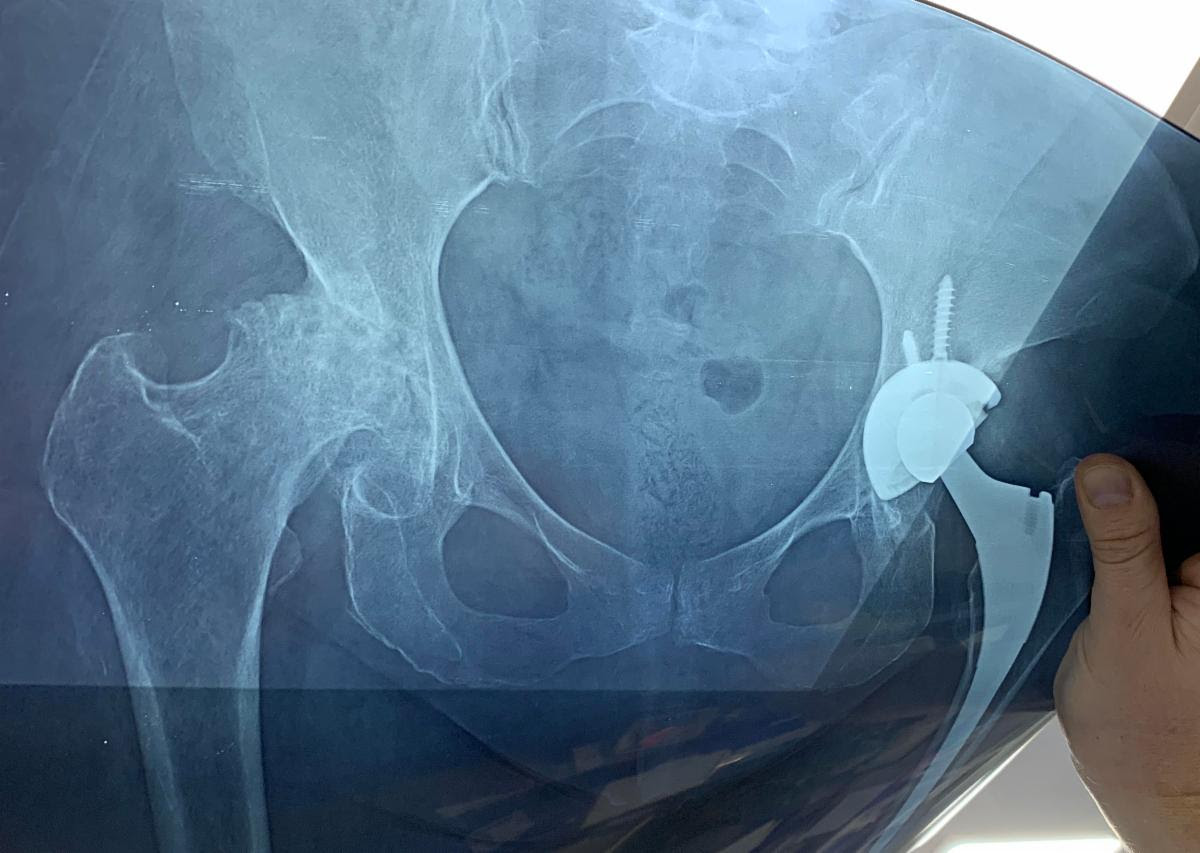

after the surgery, you can see the new replacement.